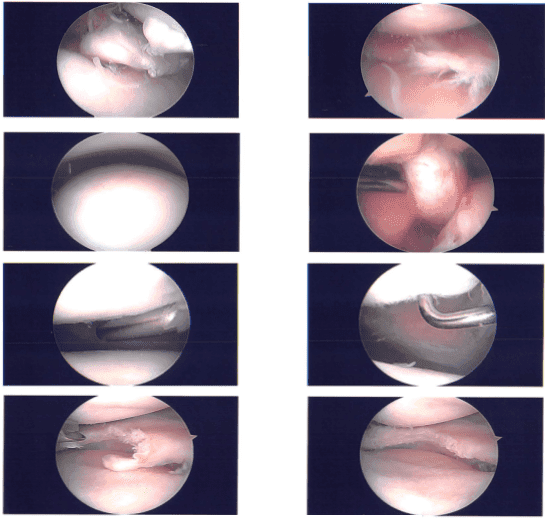

Un portal de entrada artroscópico puede realizarse a través de un portal de entrada lateral. El usuario se sentó dentro del artroscopio. Durante un examen patelofemoral se descubrieron lesiones osteocondrales de grado 1 a 2 en la parte lateral de la rótula.

Al examinar el compartimento medial, se observó una rotura del menisco medial. Se utilizaba una aguja espinal para crear un orificio de entrada medial. Cuando se insertó la sonda, una evaluación del desgarro del menisco medial reveló un desgarro lateral en el borde con un colgajo.

La raíz permaneció intacta, sin embargo, había una rotura que llegaba hasta el cuerno posterior. Se tomó la decisión de extirpar el menisco medial. Se usaron mordedores para realizar la meniscectomía medial y luego afeitadores. Se obtuvo un margen favorable.

Al examinar la muesca intercondilar izquierda se observaba un LCA intacto. Tanto el menisco lateral como el cartílago femoral lateral se observaron al examinar el compartimento lateral. Además, se introdujo el cartílago femoral medial.

Durante el examen patelofemoral se descubrió una lesión osteocondral de grado 1 a grado 2 y fue retirada con una cuchilla. El portal de entrada medial se utilizó para insertar el artroscopio, que luego se utilizó para equilibrar el menisco medial y realizar condroplastia con la afeitadora.

Se capturaron y almacenaron las imágenes finales. Estaba irrigado y drenado completamente en la rodilla. Se utilizó nylon #4-0 para el cierre. Luego se inyectó la rodilla con 9 cc de Naropin al 0,5% y 40 mg de Depo-Medrol. Se usaron ABD, Webril, Xeroform y Ace wrap para el aderezo. El paciente fue trasladado a la recuperación en estado estable tras ser extubado.

Foto clínica